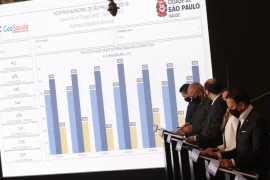

Em nova atualização, Bauru ocupa a 8ª posição no ranking de cidades que mais vacinam em SP

Governo de SP lança ranking de cidades que mais vacinam contra o coronavírus

Vacinômetro passa a divulgar o número de vacinados por município no Estado de SP

SP lança Vacinômetro para acompanhar número de vacinados em tempo real